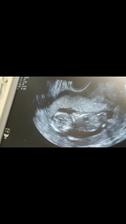

Druhé šťastie ❤

Zatial tajne dúfame,že všetko dobre dopadne..

...druhé šťastie...